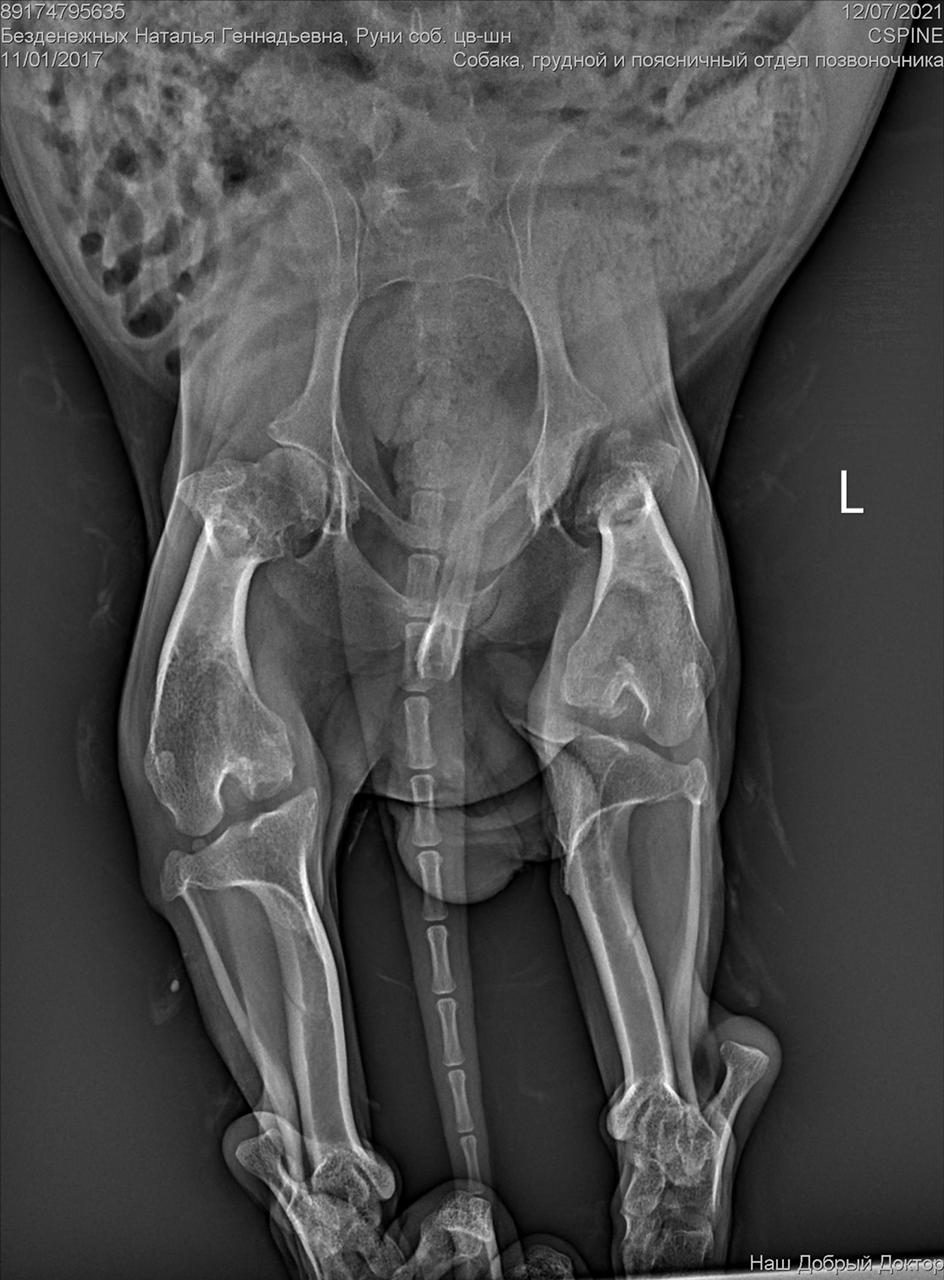

Сегодня утром под окнами дома, по адресу Дмитриева 1, был найден такой замечательный парень, задние лапы похоже перебиты, оставить умирать его я не смогла. Кто-то безжалостно выбросил маленького на улицу и оставил умирать, без еды и питья. Забрала временно к себе, сегодня повезем к ветеринару, оставить у себя возможности нет(моя собака в стрессе) , может кто то его ищет или хочет взять себе, давайте найдём пёсику дом (мама и папу)

С собакой сегодня поедут в клинику. Передержать и полечить смогут. Попросила в клинике посмотреть клеймо и посканировать ип.

ПОнадобится наша помощь с оплатой лечения и поиском дома.